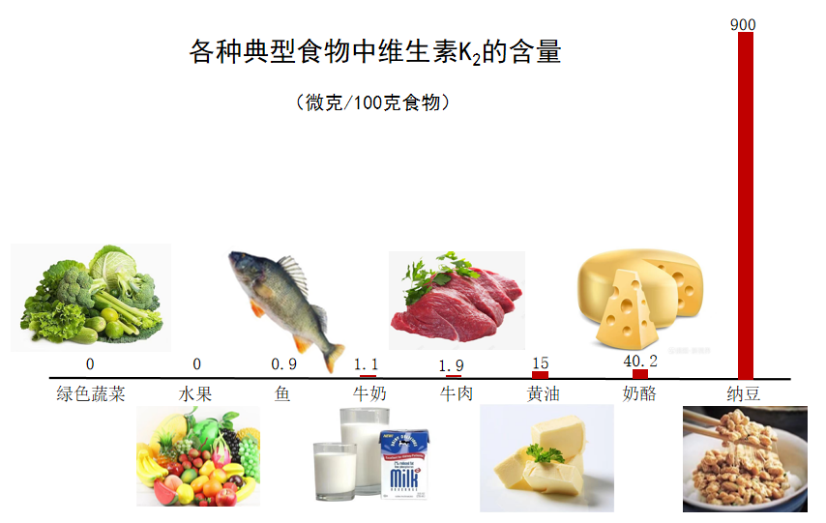

维生素K2较多存在于发酵食物中,其中纳豆含量最高,其他食物含量甚微。每天食用10克纳豆就可为机体提供足够的维生素K2。

每获取45ug维生素K2所需食物的量

在日本调查发现,食用纳豆的东京女性血液中维生素K的含量比不食用纳豆的伦敦女性高15倍。须见洋行及其同事研究证实,进食100克纳豆,4小时后血液中维生素K2的浓度最高可达原来的54倍。

典型事例:日本东部地区,当地人非常喜欢食用纳豆,每周都会食用很多次。研究发现,当地人血液中的维生素K2水平比其他地区的人高出数倍,并且他们的骨质疏松症和骨折发生率都比较低。

1995年,东京大学医学部科研人员曾对6000例60岁以上的骨质疏松症患者进行了调查研究,结果表明,服用维生素K2不仅可以减缓腰痛,而且骨骼的重量也增加了。易患骨折的人血液中的维生素K2的浓度仅是健康人的50%左右,常吃纳豆可以预防和治疗骨质疏松症。

除了食物以外,现在也有专门的维生素K2制剂。一般的药品超市都有维生素K2出售,大致分为两种,一种是从纳豆里提炼出来的天然维生素K2,规格一般使用微克(ug)计量。另一种是化学合成的四烯甲萘醌,规格一般使用毫克(mg)计量。购买的时候注意分辨。